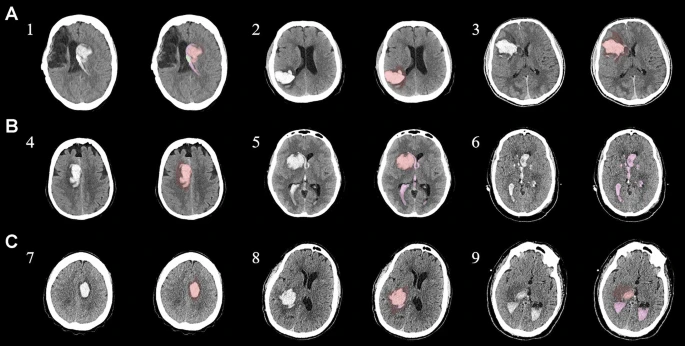

具有臨床特征的探索性成像體積模型分析

ABC/2模型1和模型2分割方法通過ICH和IVH體積的線性回歸顯示出良好的相關性(圖3a、b)。與模型2分割體積方法(例如,每個CT15-20分鐘)相比,模型1ABC/2派生的半定量方法和改進的Graeb IVH方法完成時間較短(例如,2-5分鐘)。有趣的是,NIHSS評分與IVH體積M2方法的比較顯示出線性相關性(R 2 ?= 0.7217),并且當IVH小于20mL或大于20mL時,NIHSS評分似乎出現聚類(圖3c)。PHE分析顯示MSC注射劑量和PHE體積之間存在輕微的負相關關系。

a,通過模型1ABC/2派生方法與vol模型 2(分割)進行的神經影像ICH vol的線性回歸。b、IVH通過模型1和定量分割模型2方法對Graeb進行了修改。c,出血量和NIHSS評分與IVH量通過分割進行比較。